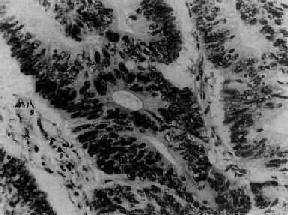

卵巢乳头状浆液性囊腺<a href=癌"/>

图13-17 卵巢乳头状浆液性囊腺

呈细乳头状结构,细胞多层,异型明显,乳头间质稀少

肉眼观,多数为多囊性,部分或大部囊内或囊外有乳头状突起,囊内多含混浊液体,乳头状物多为实性菜花状,常侵犯包膜并有出血坏死。镜下,乳头分支多或呈实心团块,上皮细胞增生多呈3层以上,细胞有明显异型性,核分裂像常见,包膜和间质均有浸润,沙粒体较多见。根据乳头状结构的分化程度可将其分为高分化、中分化和低分化3型:①高分化型(图13-17),多数乳头覆以不典型上皮,呈假复层,有一定的纤细间质;②中分化型,乳头结构仍可见,上皮细胞分化不良,呈多层,核分裂像增多;③低分化型,乳头很少,细胞呈实心片块或条索,偶尔形成腺样结构,细胞有明显异型性,包膜和间质浸润明显。